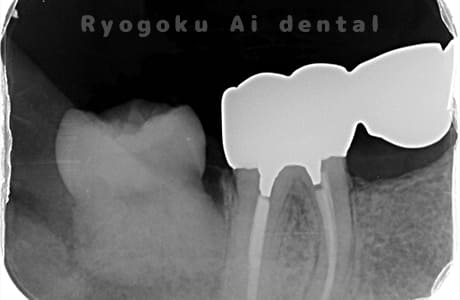

他院で右下の根の治療を行い、セラミックを被せる説明をされていたが、根の治療が終わらないため転院された患者さんです。隣の親知らずの抜歯の必要性と、根の治療を行なっている歯牙の予後が悪いため、移植治療を提案し、右下の親知らずの抜歯と同時に、右下の奥歯(7番)への移植治療を行いました。被せ物を行う必要もなく、順調に経過してます。